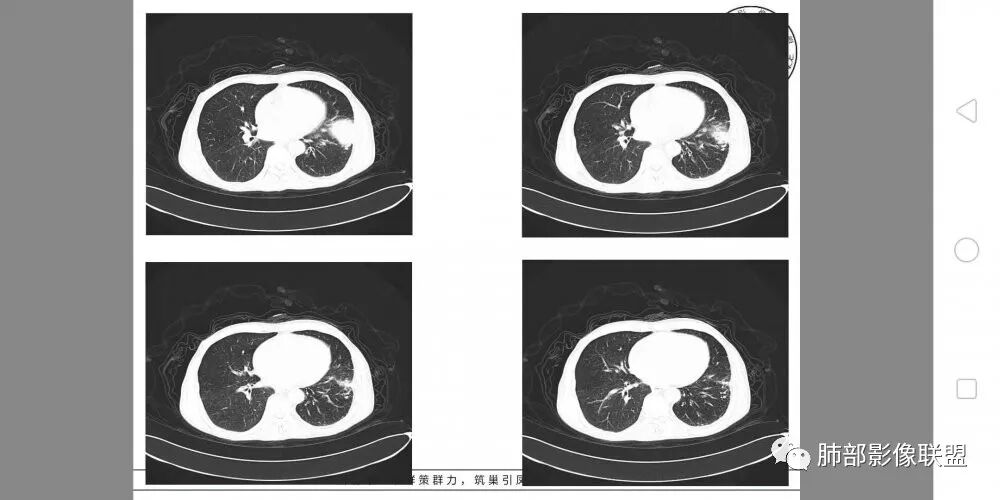

• 胸CT:左肺上叶实性占位,病灶与支气管无关,病灶对斜裂挤压,病灶周围光滑,未见分叶、毛刺;纵隔窗可见病灶内低密度区,病灶对胸壁侵袭,并可见肋骨破坏。

一切∮随缘

左肺上叶下舌段胸膜下肿块,宽基底与胸膜相连,尖端指向肺门,病变呈膨胀性生长,边缘有清晰的GGO,病灶下缘似有空泡,病灶外缘向胸壁外侵犯(有栽赃),局部肋骨有破坏,平扫密度均匀,增强后轻度强化,中老年男性,有外伤史,考虑恶性,神经鞘瘤,恶性肉瘤,恶性孤立性纤维瘤,鉴别血肿(强化不太符合)

左肺上叶占位,支气管无明显阻塞,上下舌段支气管受压推移为主,分叉角增大,胸壁受侵犯,肋骨骨质破坏,考虑肺内外朝内的病变,肉瘤样癌?

定位,肺内,左肺上叶胸膜下肿块,边缘光滑,未见分叶毛刺,支气管受压推移,有大片坏死,胸壁受侵犯,考虑恶性,肉瘤样癌?可以多平面重建看支气管跟肺内关系,如果支气管有截断,不除外磷癌

胸部CT所见左肺上叶尖后段胸膜下较大山丘形肿块,边界清楚,宽基底与胸膜相贴,边缘与胸膜呈直角及锐角相交。邻近上叶尖后段支气管受压推挤,叶裂局部膨隆,病灶周围见少许磨玻璃密度影,边界不清。纵膈窗显示,肿块密度均匀,增强扫描呈不均匀轻度强化,邻近肋骨骨质破坏,病变沿肋间隙向外侵犯,局部胸膜增厚。纵膈内见多发小淋巴结,未见胸腔积液征象。综合考虑恶性占位,肉瘤样癌可能性大。腰椎及髋部考虑骨转移。

病灶与叶裂之间夹有上叶下舌段支气管、血管。舌段支气管后移,尖后段支气管前移,病灶将支气管撑开。

叶裂受压后移,提示病灶不来源于叶裂。

支气管推移-----提示外朝内

近端肺动脉受压外移,但是有部分进入病灶内-------提示与肺有千丝万缕的关系。

不符合,因为病灶的主体在肺内,而且胸膜在病灶的外侧为主

与胸膜非钝角相交

病灶的整体形态--肺内边界清晰,膨胀性为主

如果是外面长进来的,胸膜掀起的角度一般更大,呈钝角

我们换个角度讲,如果是胸壁肋骨来源,病灶外朝内生长,并且朝内生长这么大,按理说应该是内侧侵袭性强,外侧侵袭弱。但是看这个病灶,外侧边界反而不清,内侧边界清,整个形态不太符合肋骨来源,而且胸膜局部增厚也不太符合胸壁来源。我认为肋骨来源应该以肋骨为中心,偏侧可以,但不会这么明显。而且血供也不一致,应该是肋间或胸壁动脉明显。

肋骨内侧面破坏为主,朝外有轻微的推移迹象。我觉得胸壁来源的放后面,特别是支气管的堵塞,这是肺外病变很少见的,SFT也有,罕见。